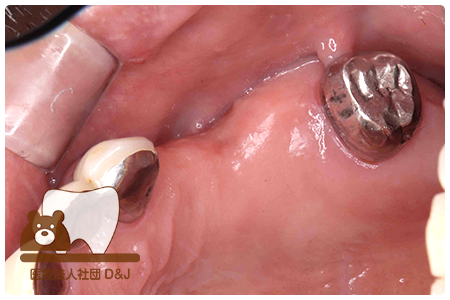

治療前

治療後

治療前

治療後

治療前

治療後

53歳 女性

- 治療内容

- 療内容奥歯にインプラントの埋入

- 治療期間

- 5ヶ月

- 費用

- 自費

インプラント体 1本:275,000円(税込)

インプラント上部構造(ジルコニア)2本:1本110,000円(税込)×2本=220,000円(税込)

(R8.3月時点)

- その他の治療の費用は含まれておりません。

- リスク・副作用

- インプラントは外科手術を伴うため、術後に腫れや痛み、出血、感染が生じることがあります。術後の指示を守らない場合、症状が悪化する恐れがあります。また、治療後に口腔内の清掃や定期的なメインテナンスを怠ると、インプラント周囲粘膜炎やインプラント周囲炎を引き起こすことがあり、インプラントの脱落につながる可能性があります。